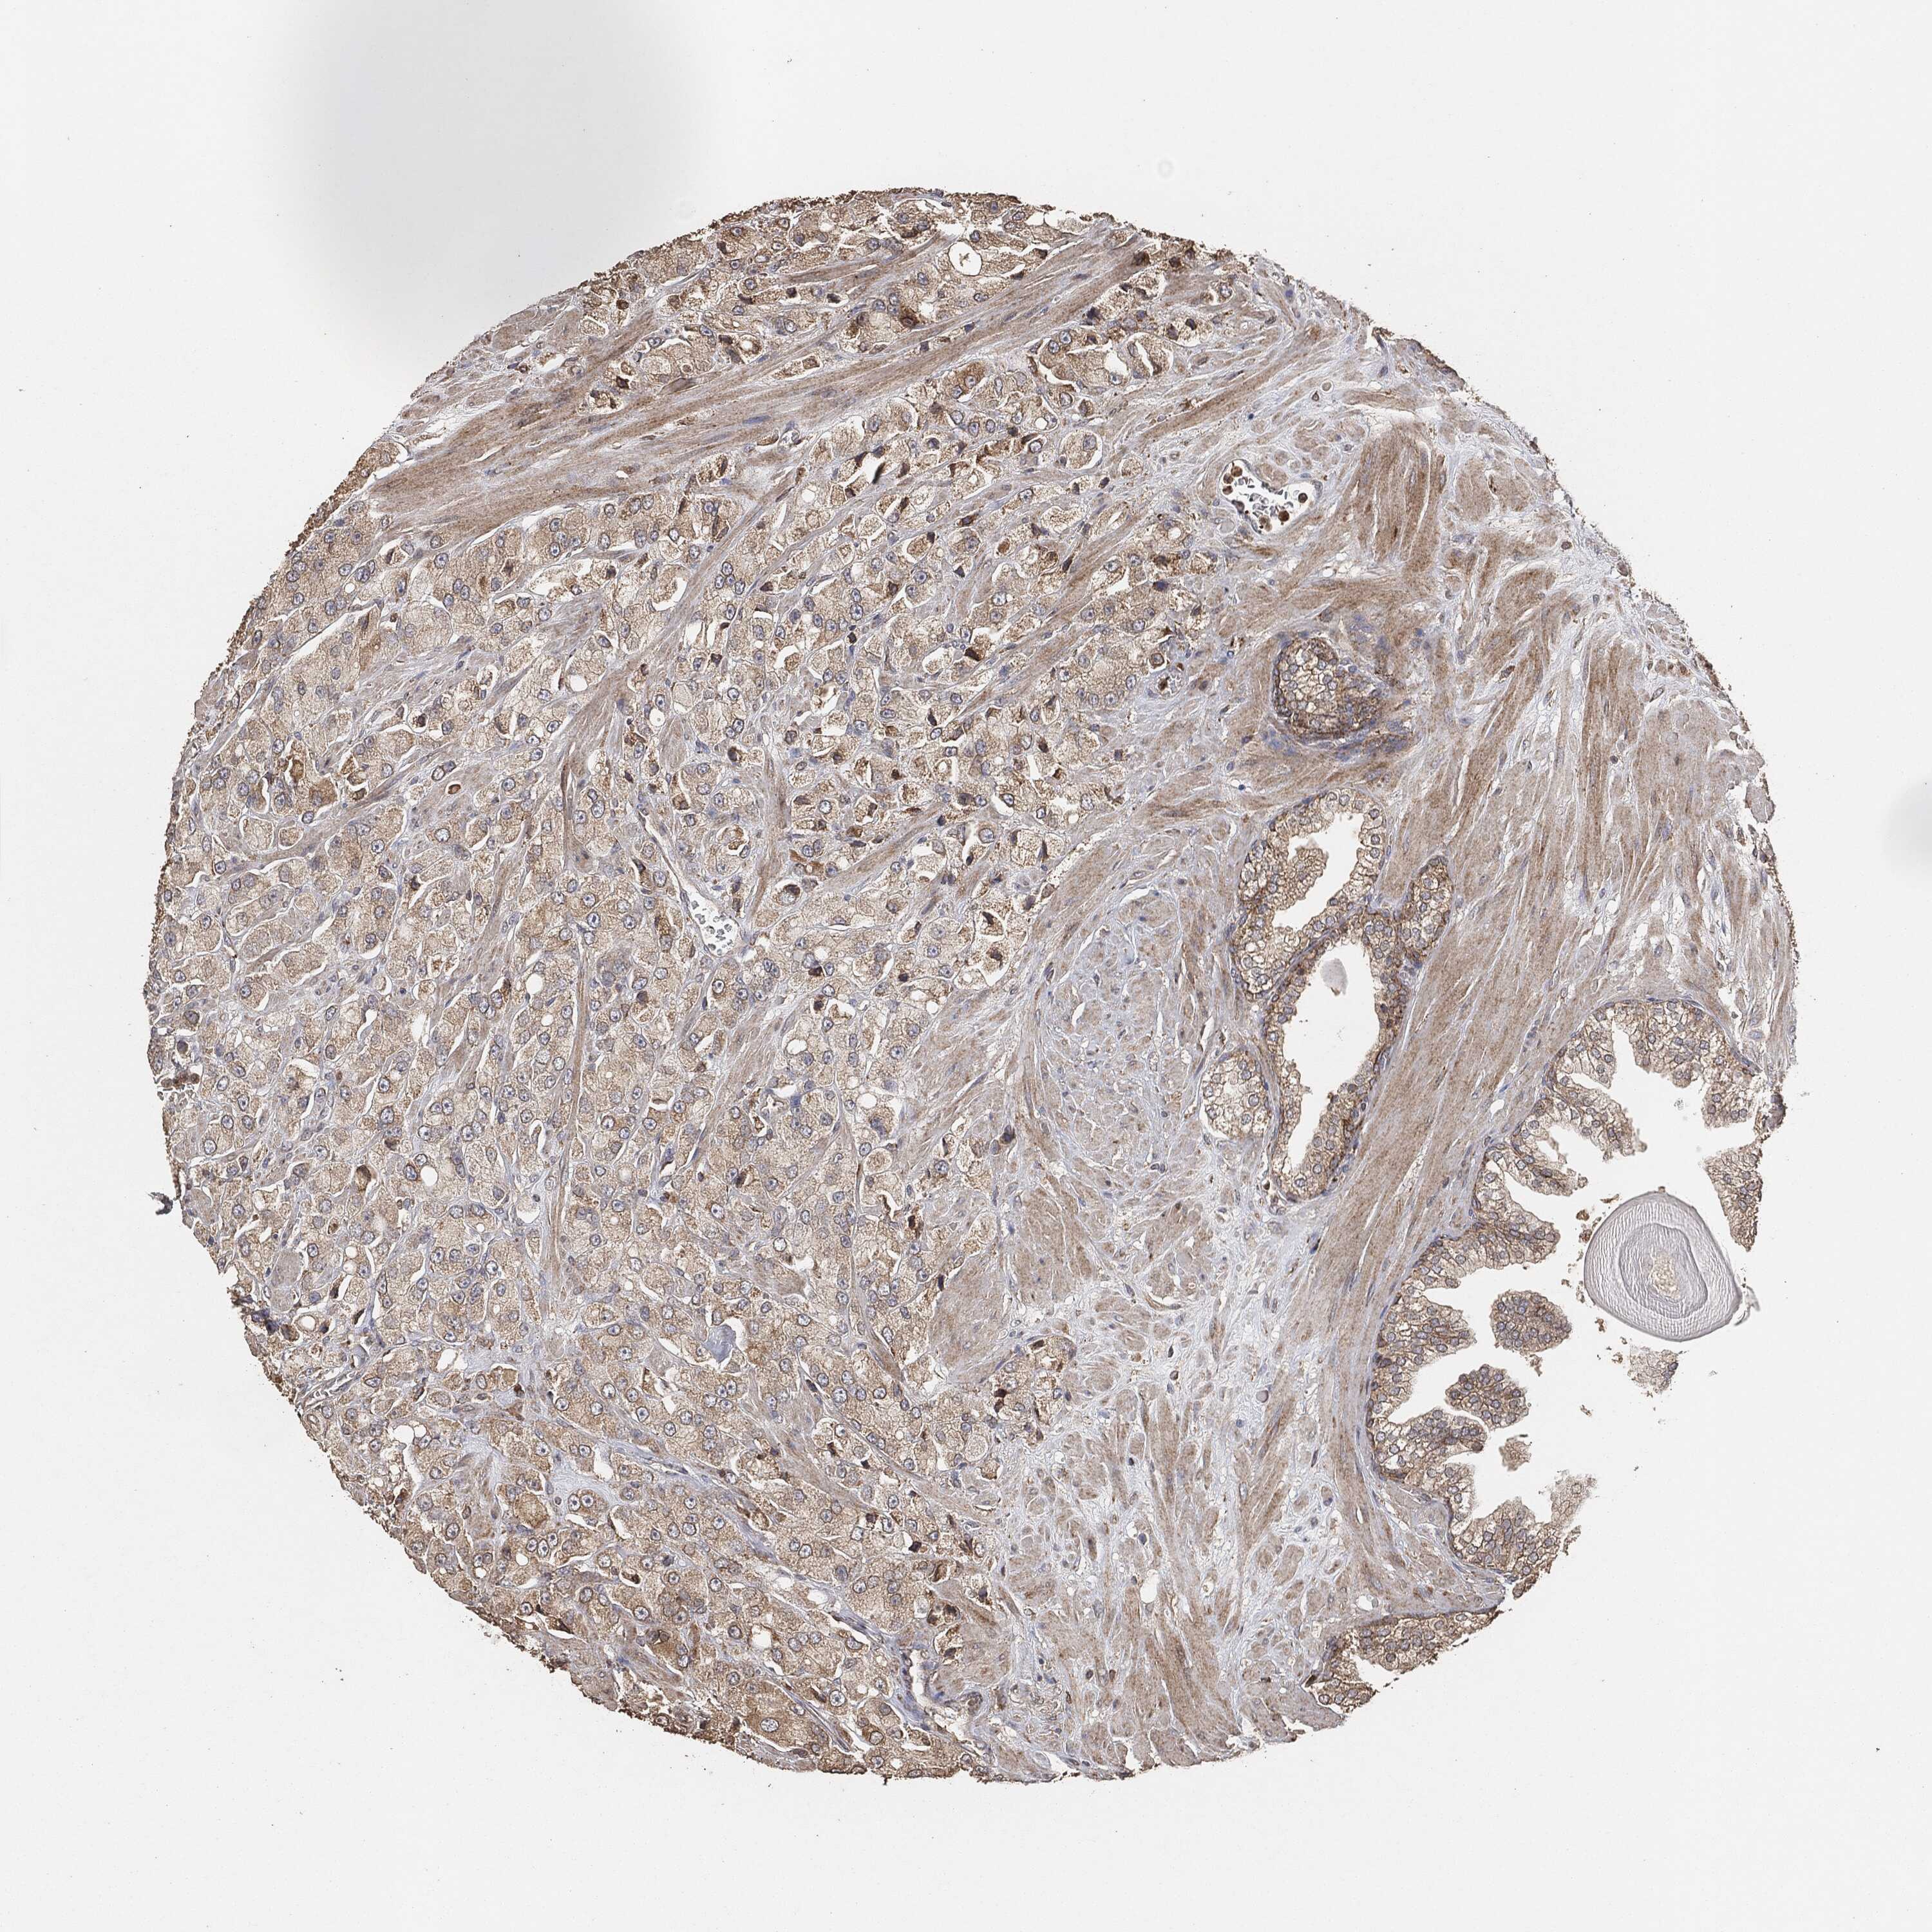

PROSTATE CANCER - Protein expressioni

A mouse-over function shows sample information and annotation data. Click on an image to view it in a full screen mode. Samples can be filtered based on level of antibody staining by selecting one or several of the following categories: high, medium, low and not detected. The assay and annotation is described here.

Note that samples used for immunohistochemistry by the Human Protein Atlas do not correspond to samples in the TCGA dataset.

Antibody stainingi

Antibody staining in the annotated cell types in the current human tissue is reported as not detected, low, medium, or high, based on conventional immunohistochemistry profiling in selected tissues. This score is based on the combination of the staining intensity and fraction of stained cells.

Each image is clickable and will lead to virtual microscopy that enables deeper exploration of all samples and also displays staining intensity scores, fraction scores and subcellular localization as well as patient and tissue information for each sample.

Adenocarcinoma, Medium grade

Adenocarcinoma, Low grade

Adenocarcinoma, High grade

Adenocarcinoma, NOS